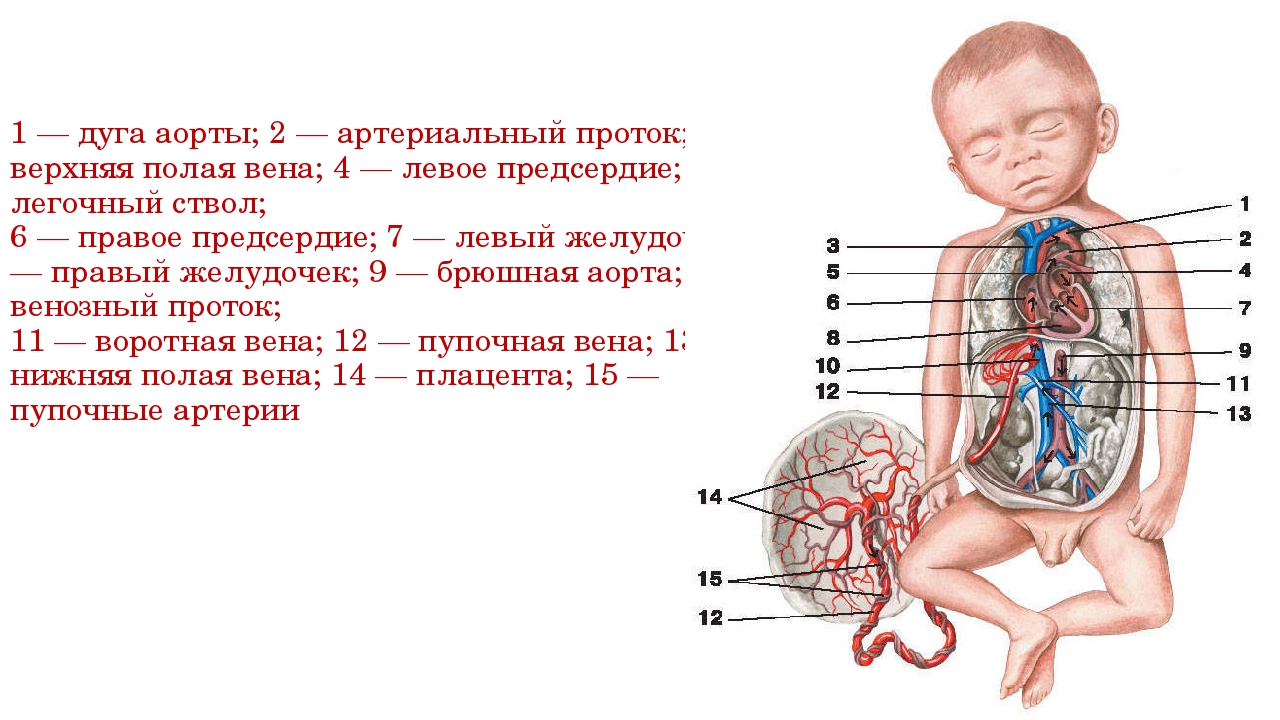

Физиология беременности: строение органов